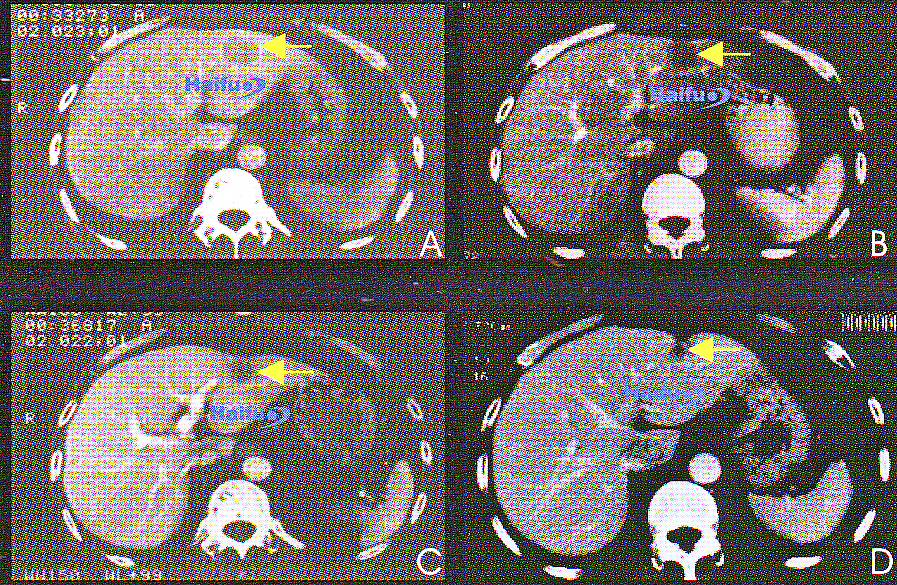

КТ-срезы с контрастированием 49-летнего пациента с гепатокарциномой, которому однократно проводился сеанс HIFU.

A) Перед лечением: визуализируется опухоль в левой доле печени (указана стрелкой) диаметром 4 см;

B) Через 3 месяца после HIFU; в опухоли отсутствует накопление контраста (стрелка);

C) Через 12 месяцев после HIFU; наблюдается уменьшение размеров опухоли, опухолевая ткань не контрастируется (стрелка);

D) Через 24 месяца после HIFU; отмечается прогрессивное уменьшение размеров опухоли (стрелка).